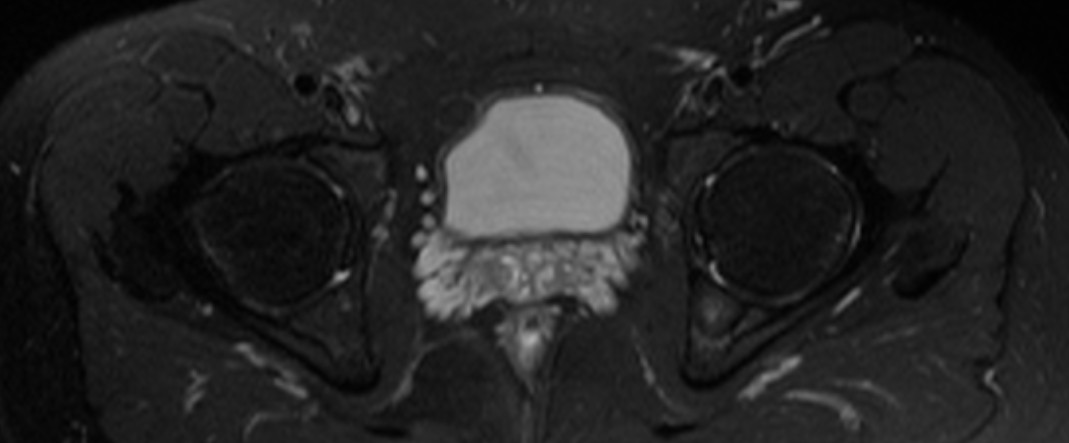

髋关节-fs T2